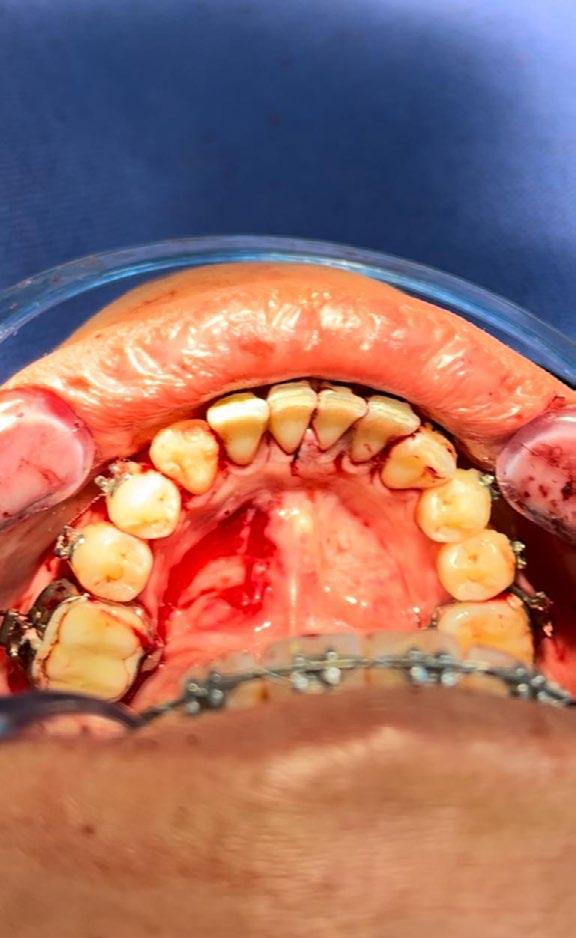

En los estudios intraorales, las fotografías iniciales muestran clase I canina y molar bilateral, mordida anterior abierta, apiñamiento leve superior e inferior, y líneas medias dentales

desviadas. En las Figuras 4, 5 y 6 se observa la forma de las arcadas superior e inferior.

Figura 6. Oclusal superior e inferior de inicio.

marginal con descarga lineal para levantar un colgajo seminewman (Figura 3). Se realiza ostectomía y osteotomía para liberar el órgano dentario retenido y facilitar su extracción (Figura 4). Una vez fuera de la cavidad bucal, se realiza tratamiento de conductos y obturación. De forma simultánea, se lleva a cabo la extracción atraumática del órgano dentario 73 (Figura 5) y la preparación alveolar del lecho receptor para recibir el órgano dentario a trasplantar bajo parámetros quirúrgicos (Figura 6).

En la zona postextracción del canino retenido (Figura 7), se realiza la conformación con materiales biocompatibles a base de xenoinjerto bovino y membrana de colágeno, para favorecer la correcta reparación de los tejidos blandos y duros, dadas las dimensiones del probable defecto, finalizando con sutura absorbible Vicryl 3-0 (Figuras 8 y 9).